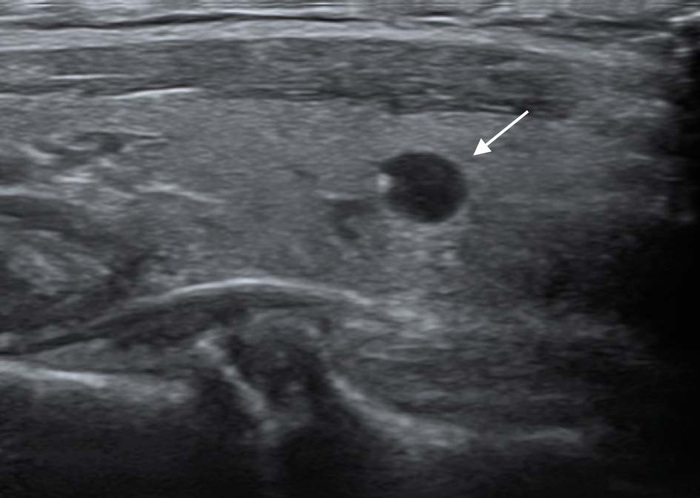

BIRADS 4 - подозрительно в отношении злокачественности. Неровные/нечеткие края, микрокальцинаты, неоднородные образования, вертикально-ориентированные образования с тенями и без попадают сюда. Как правило выполняется биопсия или пункция (вторая чаще). Выделяют еще три подкатегории, но я не стану вас этим грузить, так как даже большая часть врычей УЗИ, особенно в поликлиниках, не выставляют подкатегории.

На грани четверки и пятерки

BIRADS 5 - высокий риск злокачественности. Всякие лучистые контуры, неровные, плотные образования с тенями и т.д. попадают сюда. Биопсия при выставлении такой категории практически неизбежна.

Так же между четверкой и пятеркой, ближе к пятерке